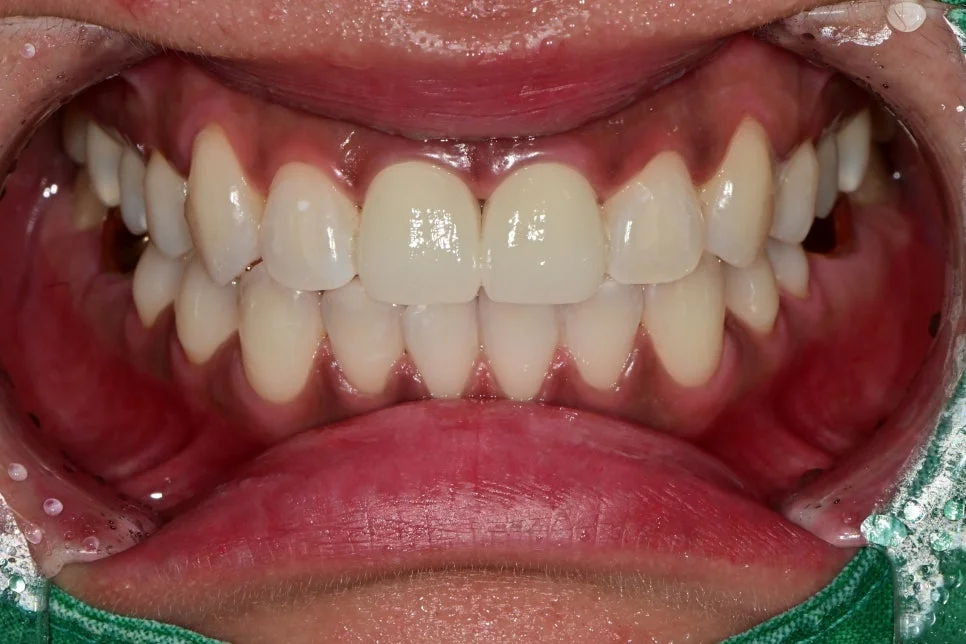

4. 크라운 세팅 및 전문가 치아미백 결과는?

이후 전치부 크라운까지 주변 치아와 긴밀하게 심미적으로도 우수하게 완성된 모습입니다.

앞니 두 개만 밝아지면 오히려 어색할 수 있어, 마지막 단계로 전악 미백(3사이클)을 진행했습니다.

치아 전체 톤이 균일하게 정리되면서 앞니 보철과의 조화가 훨씬 자연스러워졌습니다 🙂

“웃을 때 앞니 신경 안 쓰여요”라고 말씀하실 정도로 밝고 자연스러운 스마일라인이 완성되었습니다.